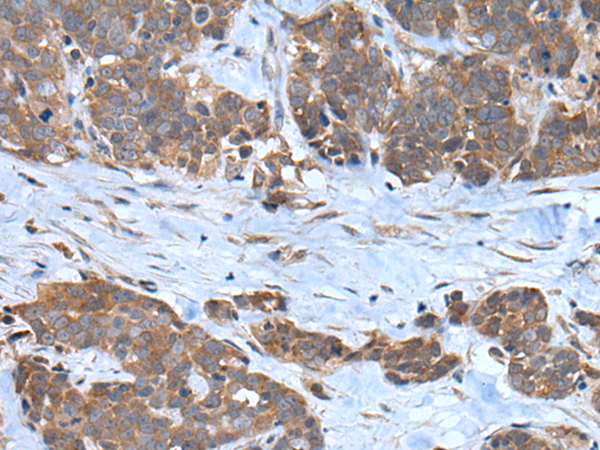

分类: 科研抗体货号: P12830别名: F3; GP135; MYPCN应用: WB,IHC反应种属: Human, Mouse, Rat